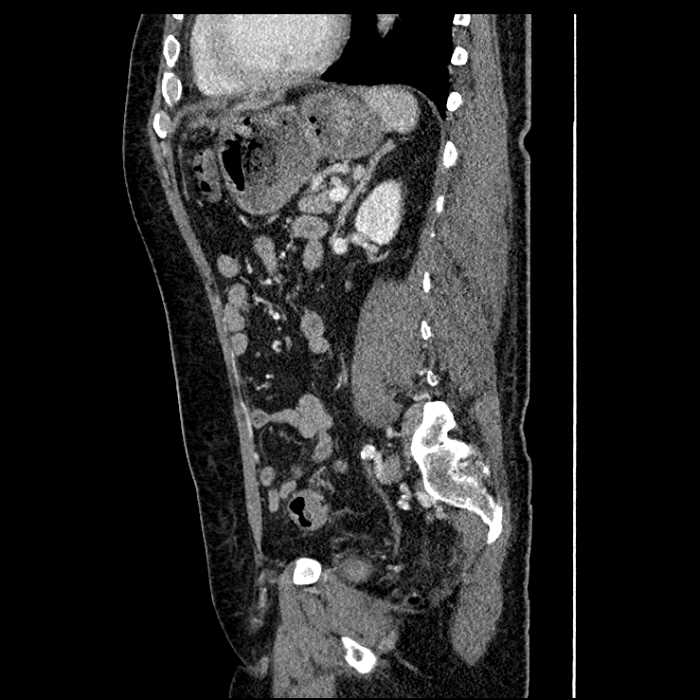

Age: 63

Sex: Male

Indication: Abdominal pain

• Large fluid density structure in hepatic segments 7 and 8 measuring 10 x 7 x 7 cm with internal septation and circumferential ill-defined low density compatible with edema

• Peripherally enhancing subcapsular collections along the anterior margin of the left hepatic lobe measuring 3 x 1 cm and 2 x 1 cm

• Clearly marginated fluid density structure in segment 7 and several other scattered tiny hypodensities, which likely represent cysts

• Mild mural thickening of a segment of the sigmoid colon with adjacent fat stranding and a 1.5 cm fluid and gas collection along the tip of an inflamed diverticulum

• Loss of the normal fat plane between this collection and adjacent loops of small bowel, which demonstrate mural thickening

Acute sigmoid diverticulitis complicated by a small contained perforation and a large abscess in the right hepatic lobe. Additional small subcapsular abscesses along the anterior margin of the left hepatic lobe.

Additionally, loss of the normal fat plane between the peridiverticular collection and adjacent thickened loops of small bowel raises the potential for an enterocolonic fistula.

• The classic CT imaging appearance is a double target sign with internal low density surrounded by an internal enhancing rim (capsule) and a low density external rim (edema)

Hepatic abscess showing the double target sign with low density internally surrounded by a thin inner enhancing rim (red arrow) and ill-defined outer low density rim (yellow arrow). Blue arrow indicates an internal septation. Red arrows: additional smaller subcapsular abscesses. Red arrow: focal contained perforation associated with diverticulitis.